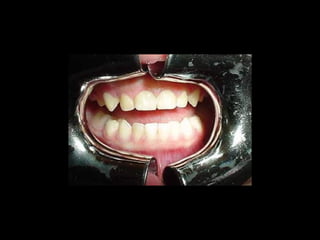

Antes (arriba) Después (derecha)

24 horas de postoperatorio

24 horas depostoperatorio